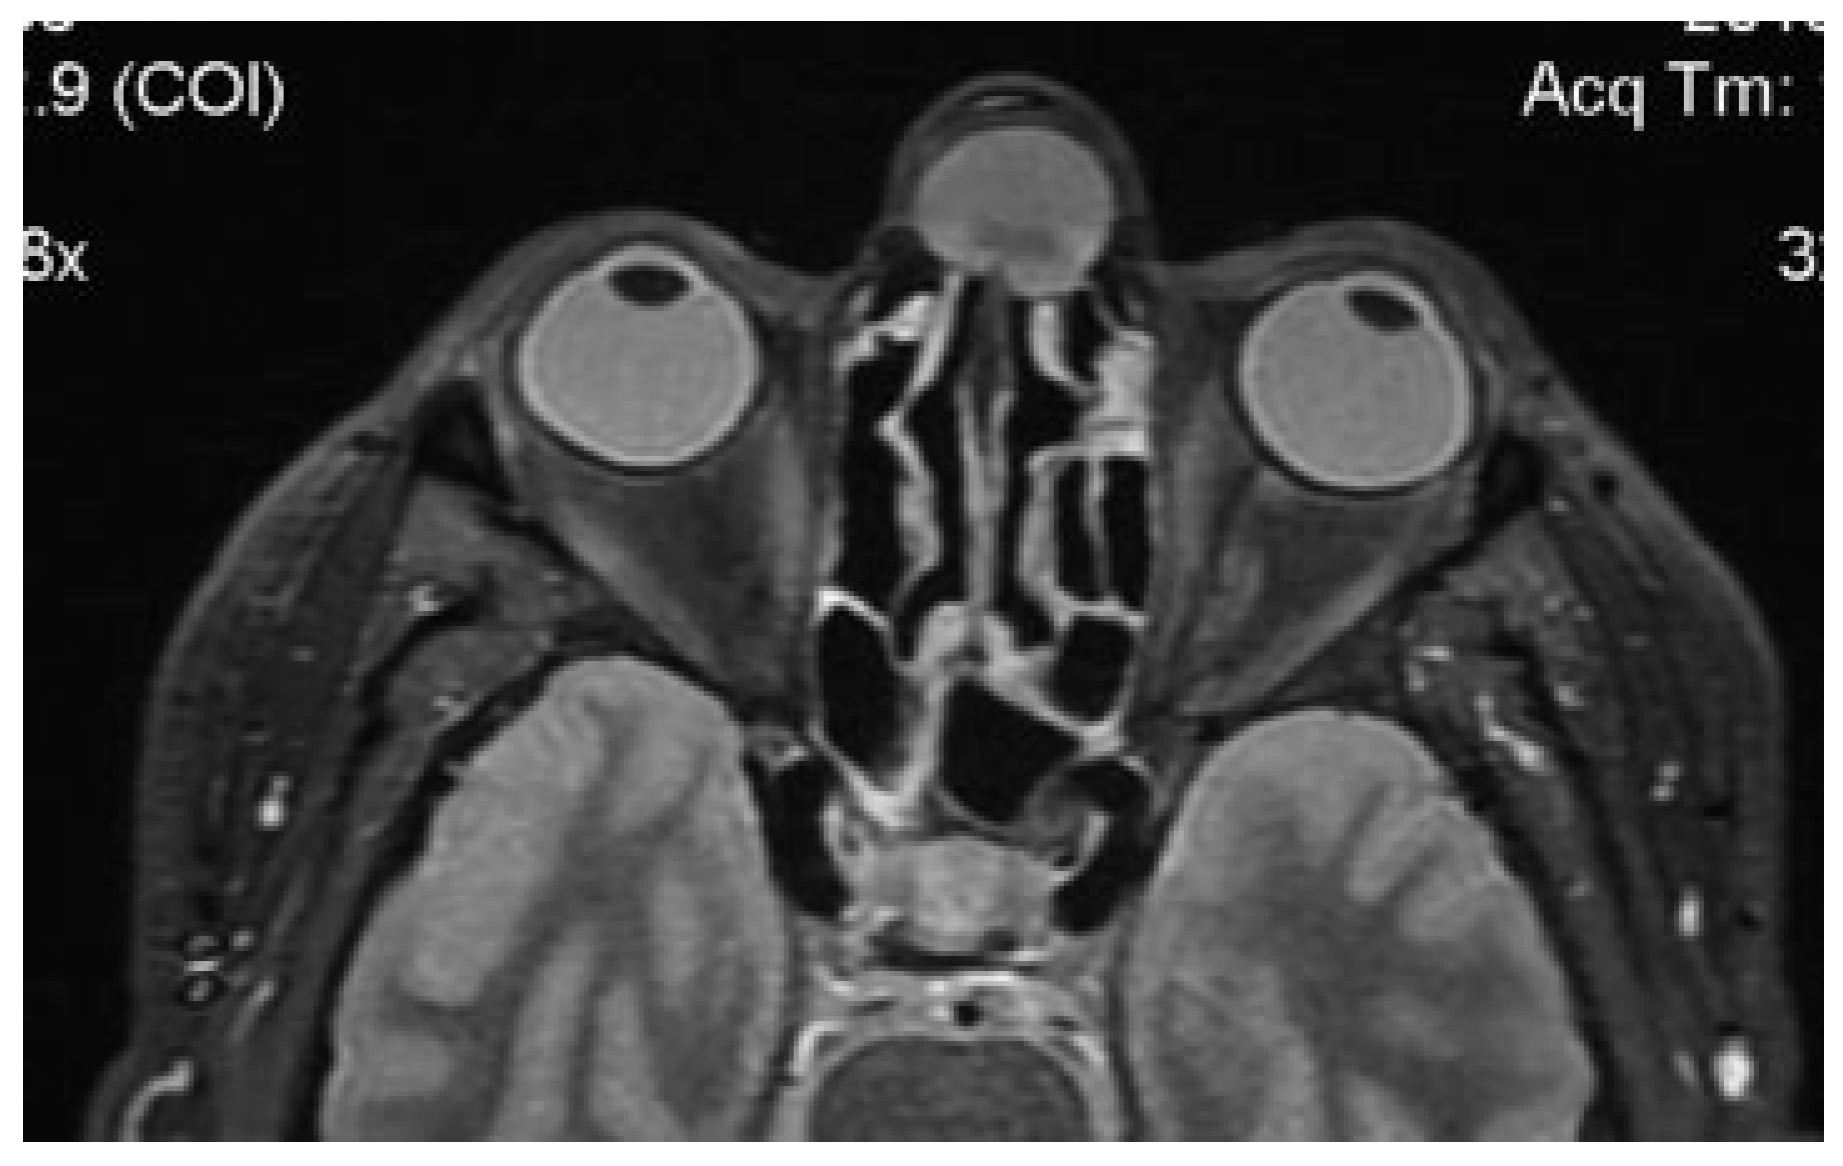

Computed tomography (CT) revealed a wide loss of substance in the root of the nose and a cystic neoformation involving the nasal bones (Figure 2). Magnetic resonance imaging (MRI) showed a globular cystic lesion with a fluid content occupying the upper region of the root of the nose and partially protruding into the nasal cavity (Figure 3). CT scan and MRI showed no involvement of the frontal sinus and frontal recess (Figure 4).

Figure 3. Preoperative MRI: globular cystic lesion with a fluid content partially protruding into the nasal cavity.